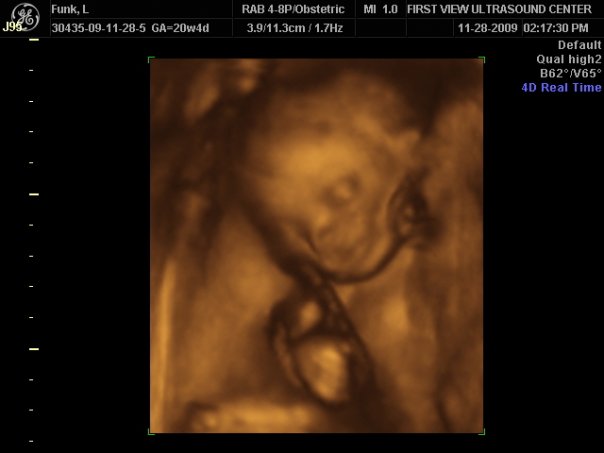

The first day of my second trimester I totally expected the morning sickness to completely disappear, but nope, I enjoyed another 3 weeks of that wonderful stuff! My baby bump showed very quickly and the baby was very active. My co-workers joked and called him a ninja basically because all he had done was kick my ass literally from day 1. I felt him move a lot and was ready to find out if he was a blue ninja or a pink ninja. At 20 weeks I went in for my ultrasound. Everything was great, baby looked wonderful, but the umbilical cord was blocking the money shot. They ultrasound tech said she was guessing it was a boy, but couldn’t be completely sure. Being the super impatient person I am when it comes to surprises, I found a place that did 3D and 4D ultrasounds and made 2 appointments! We went to the first one the Saturday after Thanksgiving; just Jason and I. It was amazing, all the little details you could see and FINALLY we got the money shot…A BLUE NINJA! I was super ecstatic! (I have always wanted boys…even if I got pregnant again I would want another boy, I just don’t think I would be a good “girl” mom.)

Blue Ninja at 20 weeks 4 Days! 3D is not recommended before 24 weeks